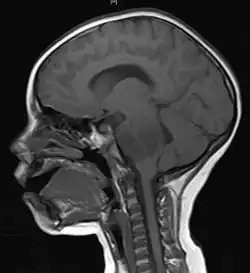

Imaging

Medical imaging plays a central role in the diagnosis of brain tumors. Early imaging methods – invasive and sometimes dangerous – such as pneumoencephalography and cerebral angiography have been replaced by non-invasive, high-resolution techniques, especially magnetic resonance imaging (MRI) and computed tomography (CT) scans.[42] MRI with contrast enhancement is the preferred imaging test in the diagnosis of brain tumors.[24][43] Glioblastomas usually enhance with contrast on T1 MRI weighted MRI imaging, and on T2 with FLAIR imaging showing hyperintense cerebral edema.[24] Low grade gliomas are usually hypointense on T1 MRI, and hyperintense with T2 with FLAIR MRI. Meningiomas are usually homogenously enhanced with dural thickening on MRI.[24]